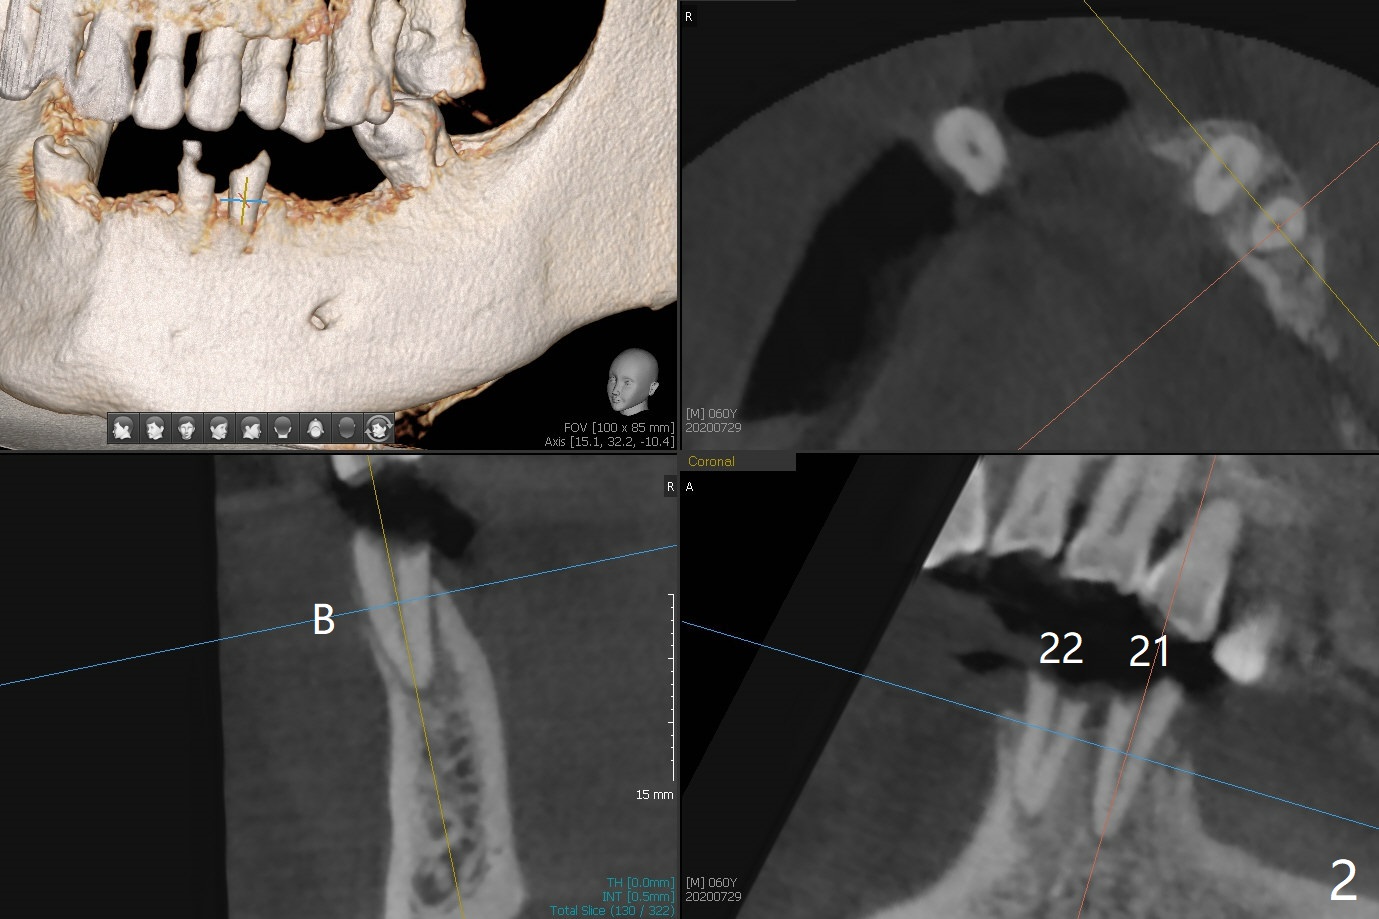

60岁男两年前回国制作下颌活动假牙,之后没有什么护理,五个基牙四个坏的厉害(图一(上面):21,22,27,31),初步计划:21,22,27号牙根管治疗(图二,三),31号牙拔除种植(申请保险,图四),都装上球状基台(ball abutment),增加托牙稳定性。当牙根基牙不行时,再逐步改做植牙。深洗和14号牙(图一)拔出后十四天病人回来进行27号牙(右下3)根管治疗(图五,六),工作长度13毫米,合适打桩做牙冠吗(原有局部托牙有卡环(Clasp and rest)?还是安置球冒更恰当?